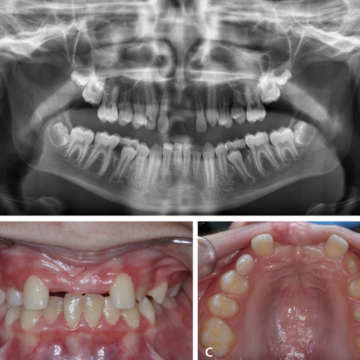

El autotrasplante dental (AT) implica la reubicación quirúrgica de un diente de un sitio de la boca a otro sitio dentro del mismo paciente. Este enfoque es una buena opción en un paciente en crecimiento cuando la colocación de implantes dentales o puentes fijos no son adecuados y cuando preservar los dientes naturales es una prioridad. El autotrasplante dental es un procedimiento complejo que requiere habilidades especializadas de un equipo multidisciplinario con una cuidadosa selección de pacientes y dientes y planificación del tratamiento.

Las tasas de éxito de la AT dental pueden variar según varios factores, incluida la salud general del paciente, el diente específico involucrado, la habilidad del cirujano dentista y la atención posoperatoria brindada. En la literatura se han citado los resultados a largo plazo de los dientes autotrasplantados con un seguimiento longitudinal impresionante que abarca hasta 26 años. Los resultados de varias revisiones sistemáticas mostraron tasas de supervivencia del 75% al ​​98%.

La adopción de la AT dental ha crecido a lo largo de los años, debido a los avances en las técnicas dentales, mejores resultados para los pacientes y una mayor concienciación tanto entre los dentistas como entre los pacientes. Aumentar la conciencia y la disponibilidad de la AT dental para reemplazar los dientes perdidos puede proporcionar una alternativa natural y funcional a las opciones protésicas tradicionales. El AT ayuda a preservar el hueso alveolar en pacientes en crecimiento y puede ofrecer excelentes resultados estéticos y funcionales.